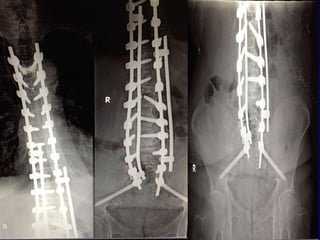

Πρόσθια – Οπίσθια

Διόρθωση και Σπονδυλοδεσία

15yrs F- up